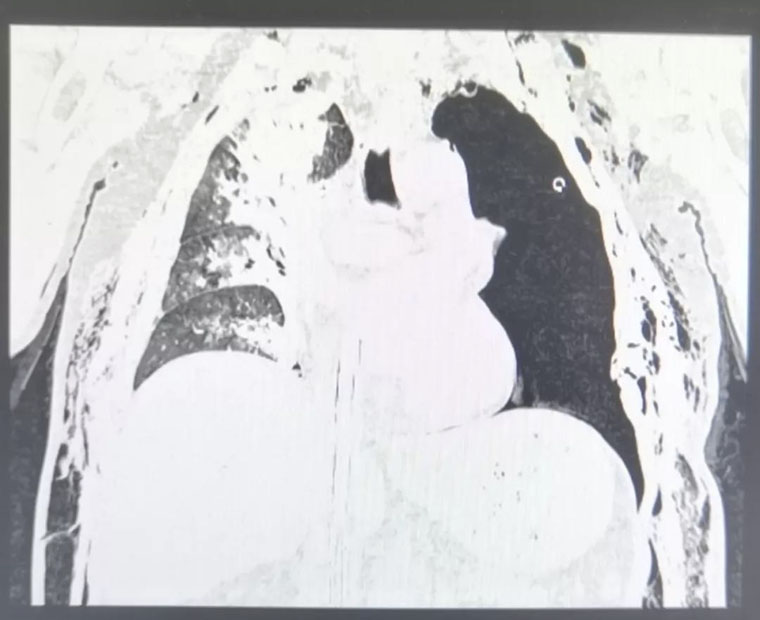

患者的胸部CT

然而,大量的气泡从胸腔闭式引流管喷出,我们意识到,这样下去肯定不行,带ECMO做CT检查,再次请胸外科会诊,讨论手术的必要性。